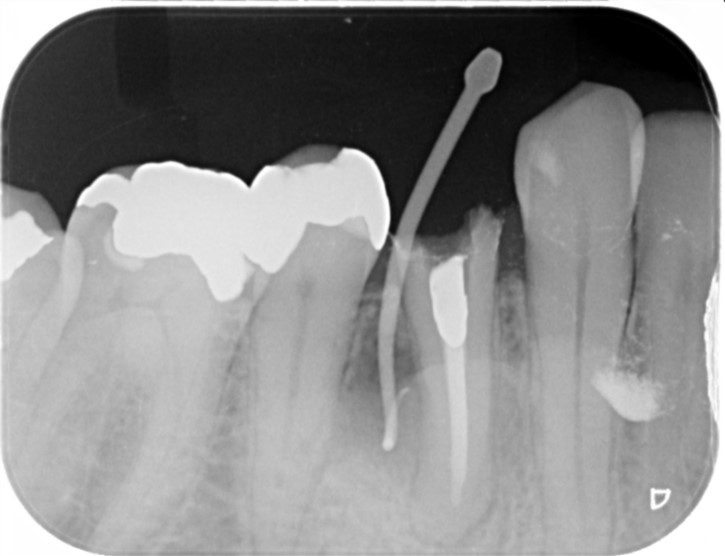

Case

インプラント治療 右下奥歯 左上奥歯

歯の治療の開始前で右下と左上に歯がないところがあります。

治療を開始させていただく前のお口の中の状態です。

インプラント治療終了後3年の経過良好の状態です。

現在のお口の中の状態です。歯がないところに歯を回復させていただきました。

治療部位 | 右下76(インプラント+ジルコニア) |

費用 | (495,000円×4)約200万円 |

治療期間 | 6か月 |

下の奥歯がなく、食べにくいため、食べやすい治療方法を希望。

また、残っている歯に対する影響の少ない治療方法を希望され、インプラントを選択。